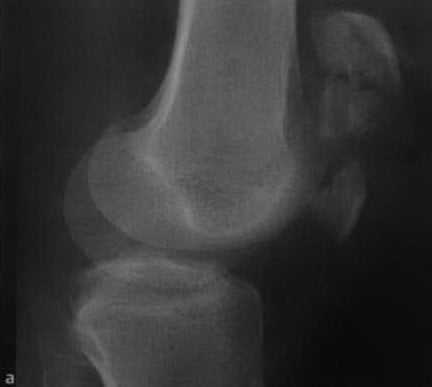

(Справа) При рентгенографии в боковой проекции у этого же пациента определяется поперечный перелом нижней поверхности надколенника с отсутствием смещения. Поперечные переломы иногда возникают вследствие насильного разгибания при сокращении четырехглавой мышцы. (Слева) На рентгенографии в передне-задней проекции определяется продольный перелом надколенника вследствие прямого удара. Острые края перелома позволяют отличить такую травму от надколенника, состоящего из двух частей.

(Справа) МРТ, выполненная после падения на колено, РDВИ, режим подавления сигнала от жира, аксиальный срез: определяется продольный перелом надколенника. Края осколков перелома острые, в них отсутствуют признаки склероза. Отмечается обширный отек костного мозга и разрыв суставного хряща. (Слева) При рентгенографии в передне-задней проекции определяется надколенник, состоящий из двух частей. Края дополнительного центра окостенения гладкие и ровные. Дефект надколенника зачастую крупнее чем вторичный центр, в отличие от перелома, который бы соответствовал по размеру.

а,b Оскольчатый перелом надколенника со смещением. Рентгенологическое исследование надколенника в боковой (а) и прямой (b) проекциях. Звездчатый перелом с расхождением фрагментов проксимально и дистально.